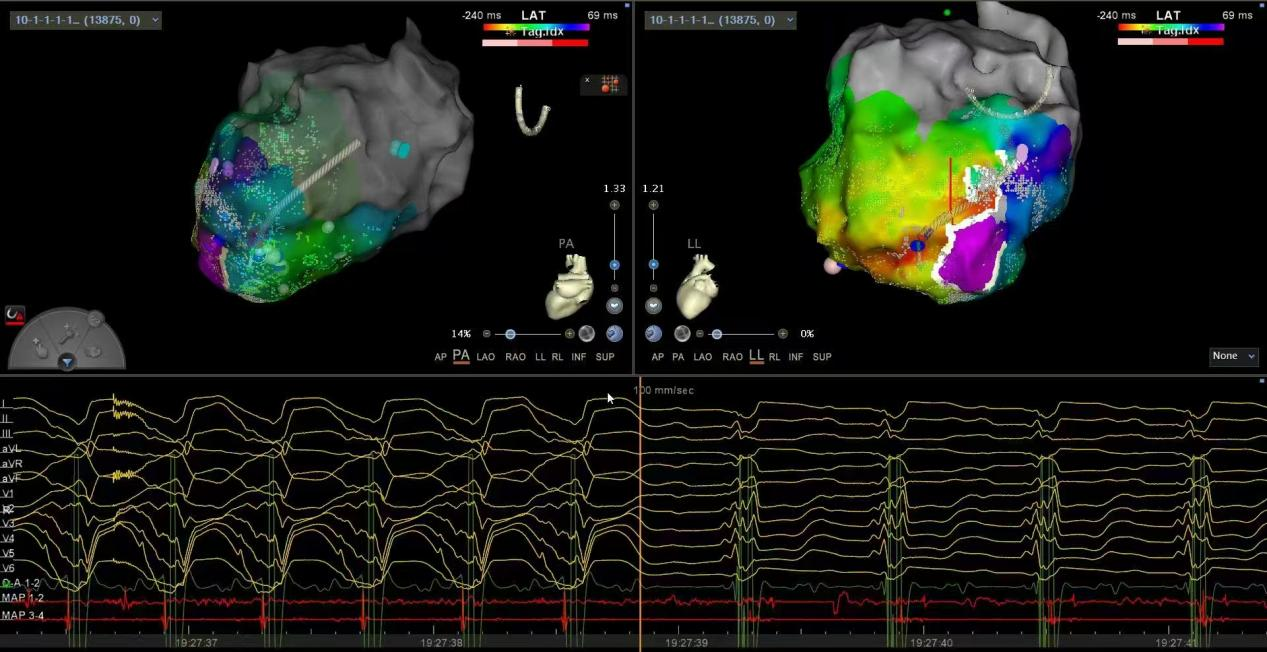

超高精密度标测指导下的器质性室速消融术

ü建立超高精密度标测指导室速消融新技术,累积完成3例国内超高难度器质性室速消融(其中两例为电风暴),术后无一例室速复发,提升疑难心律失常诊治水平!

ü全球率先心内外联合治疗双瓣置换术后器质性室速病例。

ü心内、外科强强联合,内膜外膜联合标测消融,成功完成一例超大左室,主动脉瓣置换术后,反复室速发作,ICD反复放电,更换起搏器后又面临电池耗竭的重症患者。该患者心脏移植排队一年无望,射频消融为其重启生命动力。